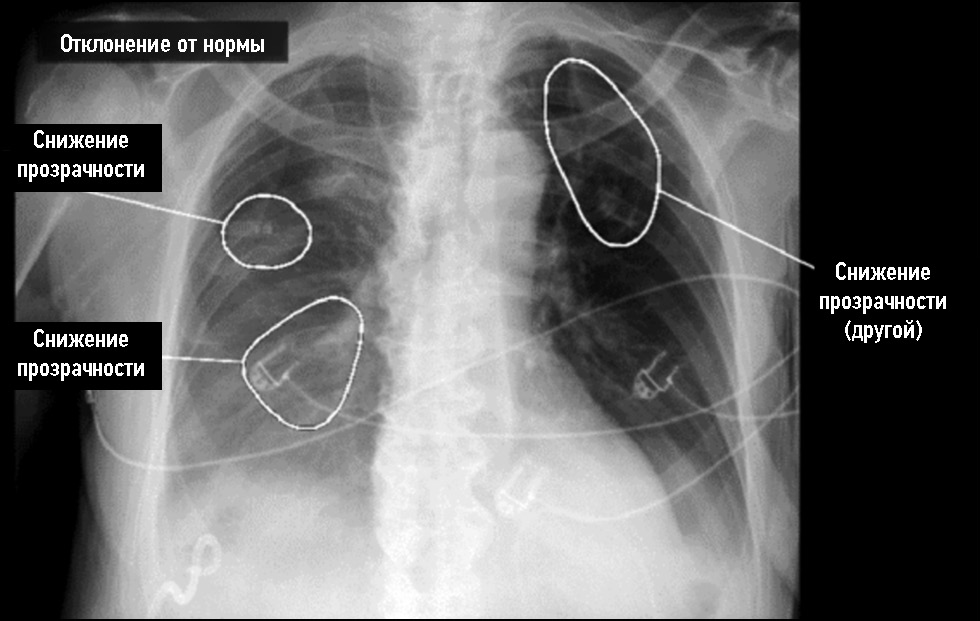

Несомненным и самым существенным минусом применения технологий компьютерного зрения при анализе рентгенограмм органов грудной клетки как самостоятельного механизма является невозможность оценки сервисом ИИ динамики патологического процесса, поскольку ПО на основе ТИИ имеет доступ только к текущему исследованию, вследствие чего возрастает вероятность необоснованного дообследования пациентов со «старыми» изменениями в лёгких, такими как кальцинаты, фиброзные лёгочные и спаечные плевральные изменения [21]. В ряде случаев «старые» спайки в косто-диафрагмальных плевральных синусах интерпретируются и маркируются ПО на основе ТИИ как свободная жидкость в плевральной полости, что легко опровергается при пересмотре данных предыдущих исследований пациента непосредственно врачом-рентгенологом. Таким же образом врач-рентгенолог может оценить фиброзные изменения, кальцинаты, наслоения на костальной плевре, не изменяющиеся в динамике и не требующие повышенного внимания со стороны клинициста. При проведении данного исследования был выявлен случай ложноположительной оценки ПО на основе ТИИ старых участков линейного фиброза как участков затемнения, в то время как врач-рентгенолог не счёл необходимым указать их наличие, также имеется один случай ложноположительного срабатывания на участки старых плевральных наслоений, которые ПО на основе ТИИ определил как лёгочные узлы, и, кроме этого, имеется один случай ложноположительного срабатывания, связанный с наличием уплотнения в Ι ребре, которое ПО на основе ТИИ определило как лёгочное затемнение. Отдельно следует упомянуть об одном случае обнаружения старых метатуберкулёзных изменений, не являющихся действительно ложноположительными, которые ПО на основе ТИИ выявило, но не смогло правильно интерпретировать в связи с отсутствием полной динамической картины (рис. 4).

Рис. 4. Поствоспалительные изменения, фиброз, плевро-паренхиматозные тяжи, спайки.